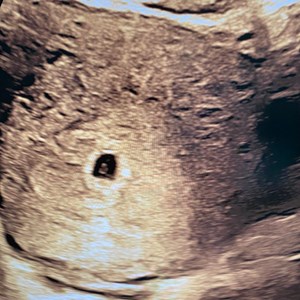

8. juni 2024

Den livsændrende oplevelse 💖 Det her billede viser for de fleste bare en mørk plet. Men ...